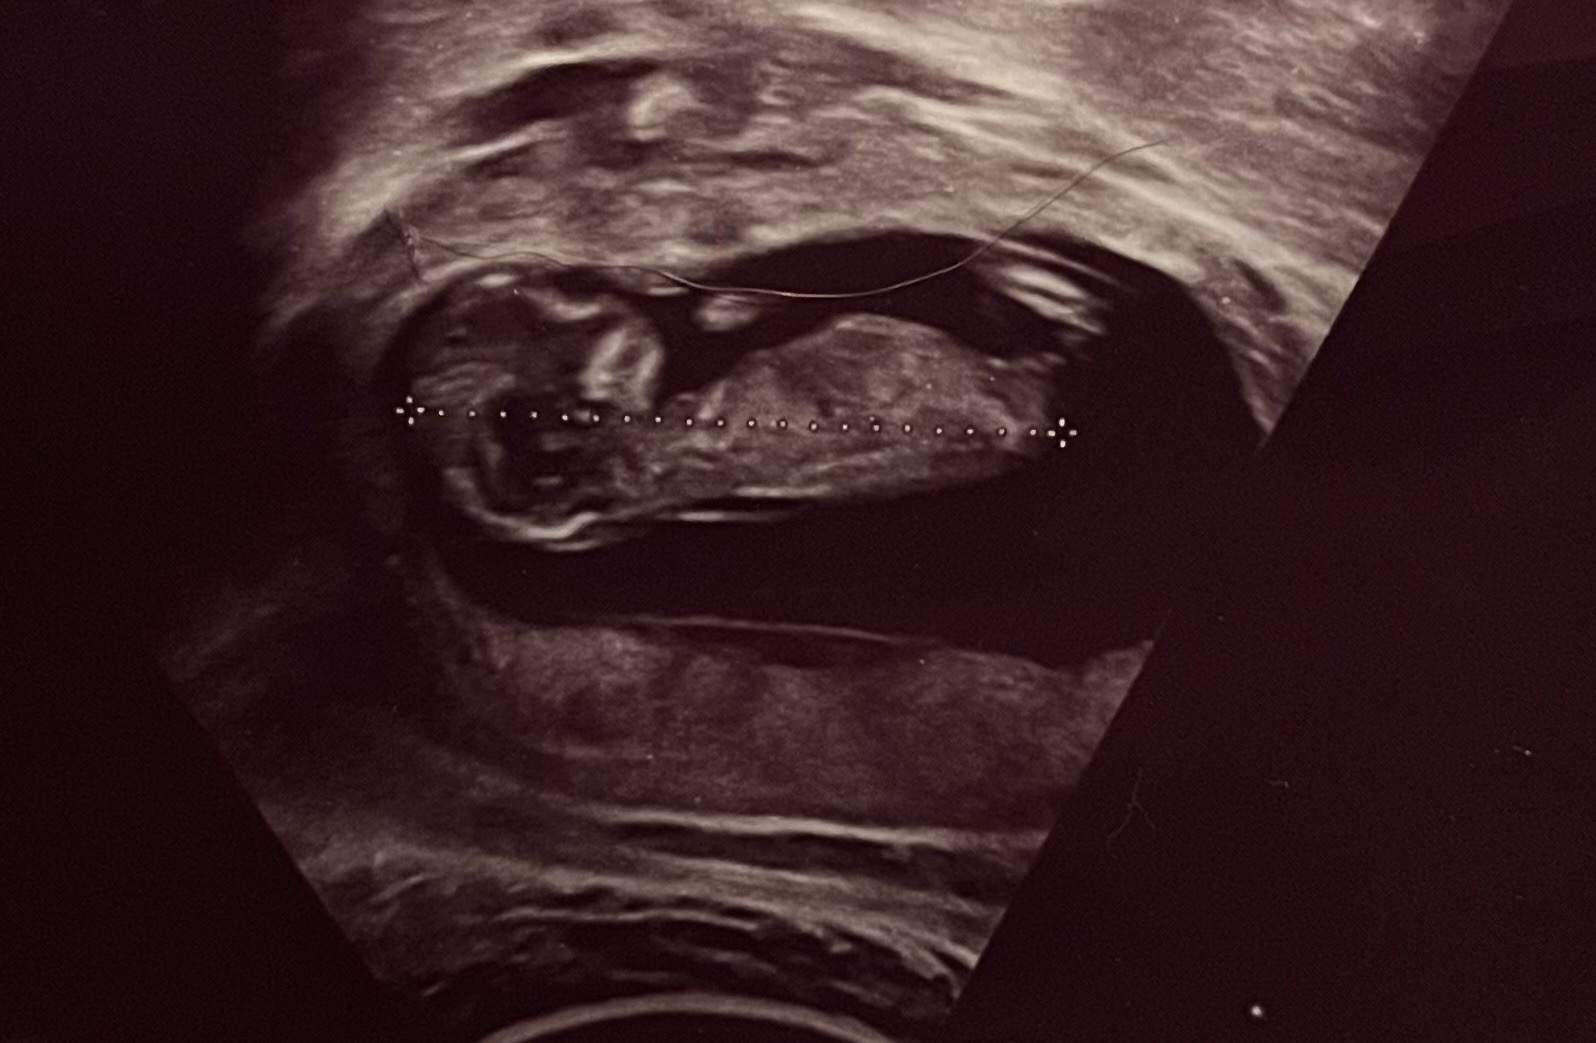

각도법 투표해주세요 12주0일 입니다